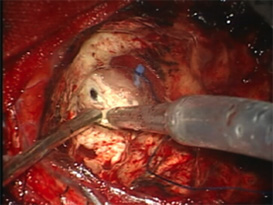

蛍光診断(光線診断) PhotoDiagnosis(PD)

脳腫瘍、特に神経膠腫(glioma)では摘出術中に正常の脳組織との区別が難しいことがしばしばあります。そのような場合には、脳腫瘍かと思って切除したら大事な正常脳組織であったり、また正常組織かと思われた部分が脳腫瘍の一部であるということが術後のMRI検査でわかるということもあります。これを防ぐために用いられる方法が蛍光診断です。

手術前にアミノレブリン酸というお薬をブドウ糖に溶かして内服していただきます。そして手術中に脳腫瘍のあたりに青い光を当てると腫瘍だけが赤く光って見えます。

(左図)腫瘍を摘出後

(右図)青い光を当て、残存腫瘍だけが赤く光る。

この赤く光った部分を摘出すれば腫瘍の摘出が完了します。